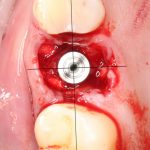

Рекомендации по установке имплантов. Для всех. Часть V.